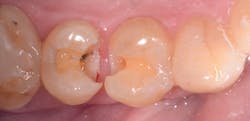

The placement of posterior composites has often troubled dentists. They can be time-consuming, technique-sensitive, and costly to do. There are a number of composites on the market that claim to be "bulk fill," implying we can reduce or eliminate multiple increments of applications. If that's the case, we would be able to tackle our operative dentistry more efficiently and more predictably. Fortunately, some bulk fill composites are "true" bulk fill composites that have the necessary ingredients to deliver on that promise. Let's look at the trials and tribulations of placing posterior composites and compare them to using Tetric EvoCeram Bulk Fill.

The stress relievers that are part of the new filler technology mean I am putting less stress on the composite, which leads to a number of advantages as well. Postoperative sensitivity is decreased due to less stress on the tooth. Also, the margins do not get the dreaded white line, indicating the bond is breaking down from too much shrinkage.